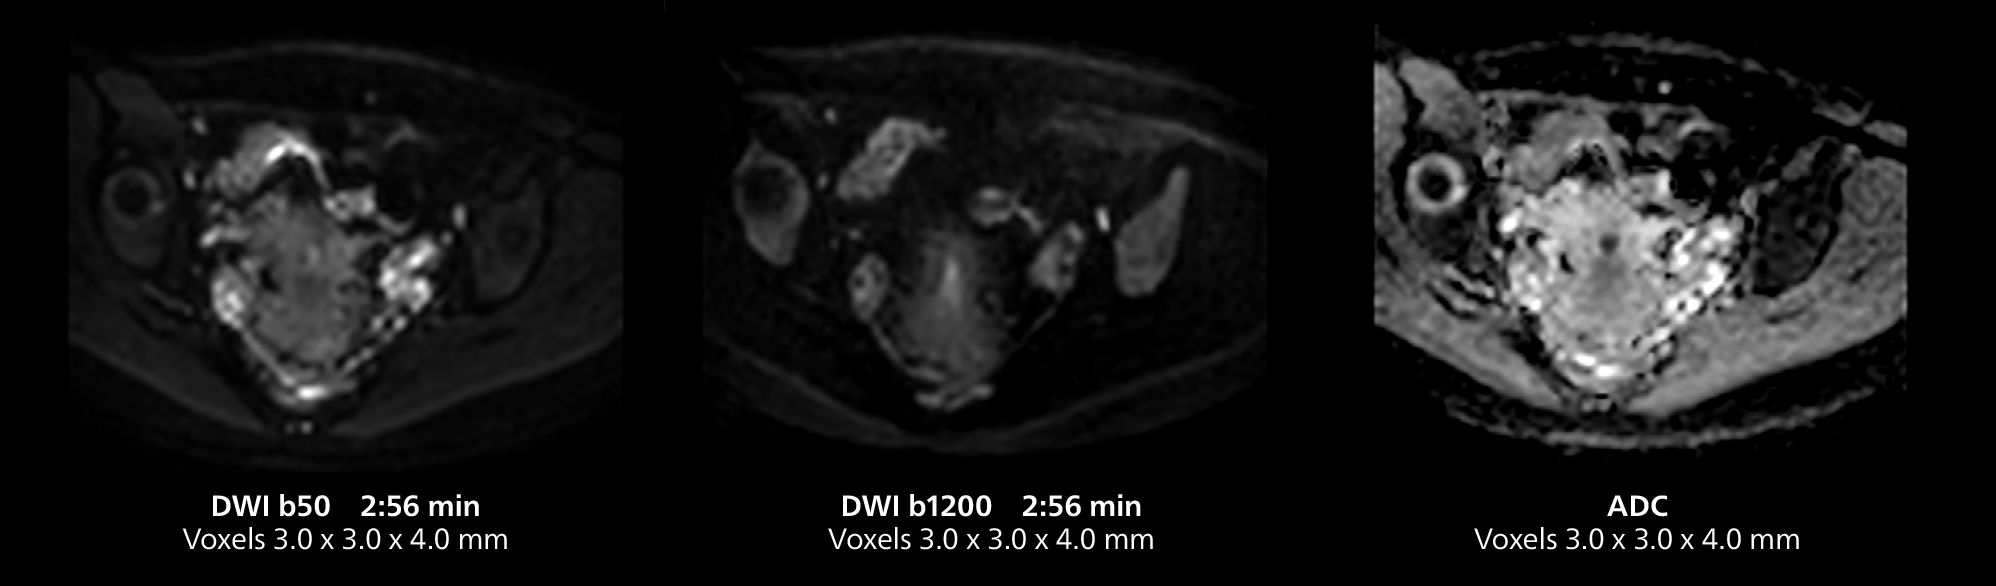

Female pelvis imaging

This MRI case illustrates good resolution and imaging quality obtained within reasonable scan times using the MR 5300 1.5T system with the anterior torso cardiac coil that allows use of a large field of view (FOV).

Pelvis mri one

Pelvis mri two

Pelvis mri three